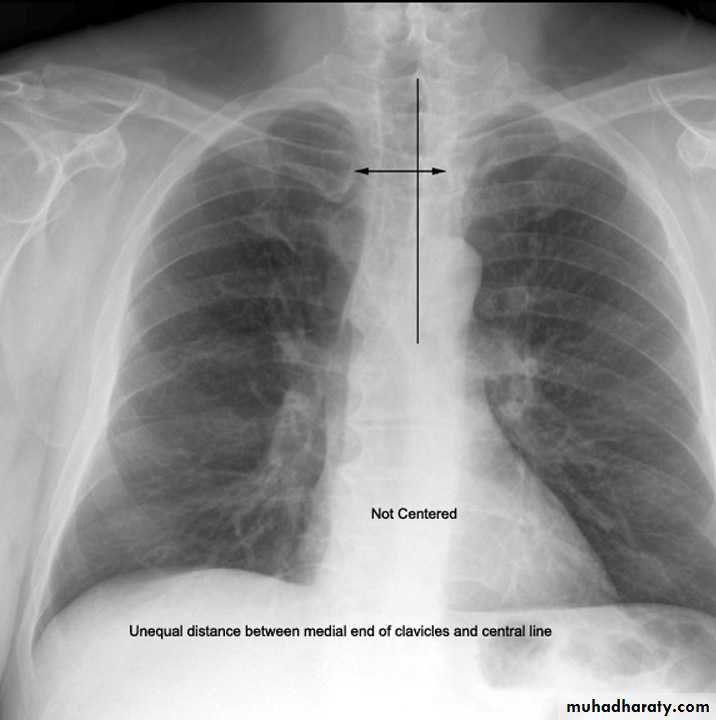

6) Good centering ( not rotated )

Both medial ends of clavicles are equi-distance from spinous process of adjacent vertebra .In rotated film , one side of the lung appear more opaque than the other with distortion of mediastinal borders.

Rotation .

Rotation of the radiograph is assessed by judging the position of the clavicle heads and the thoracic spinous process.7) Good technique (amount of radiation )